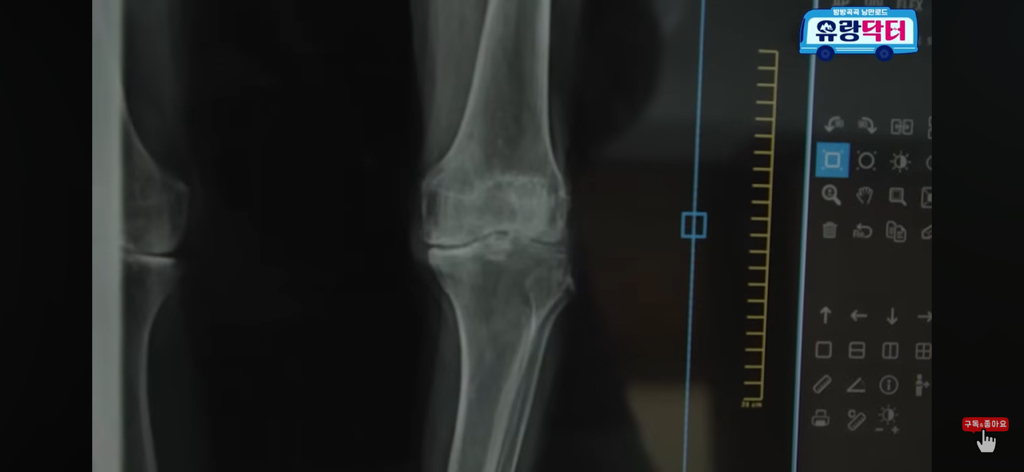

허리가 완전 90도로 굽은 할머니

20년 넘게 뼈가 굳어서 죽었다고 말씀하심

+ 찾아보니까 FIMS 치료라고 하고

1번으로는 효과 기대하기 힘들고

3번은 받으면 그래도 점차 나아지긴 한대

근데 3번 정도 받는다고 완전히 펴지는 건 아니고

90도가 60도 되고 60도가 30도 되고

그렇게 점차 효과를 보는 치료인 것 같음

한 번만으론 절대 안 됨!